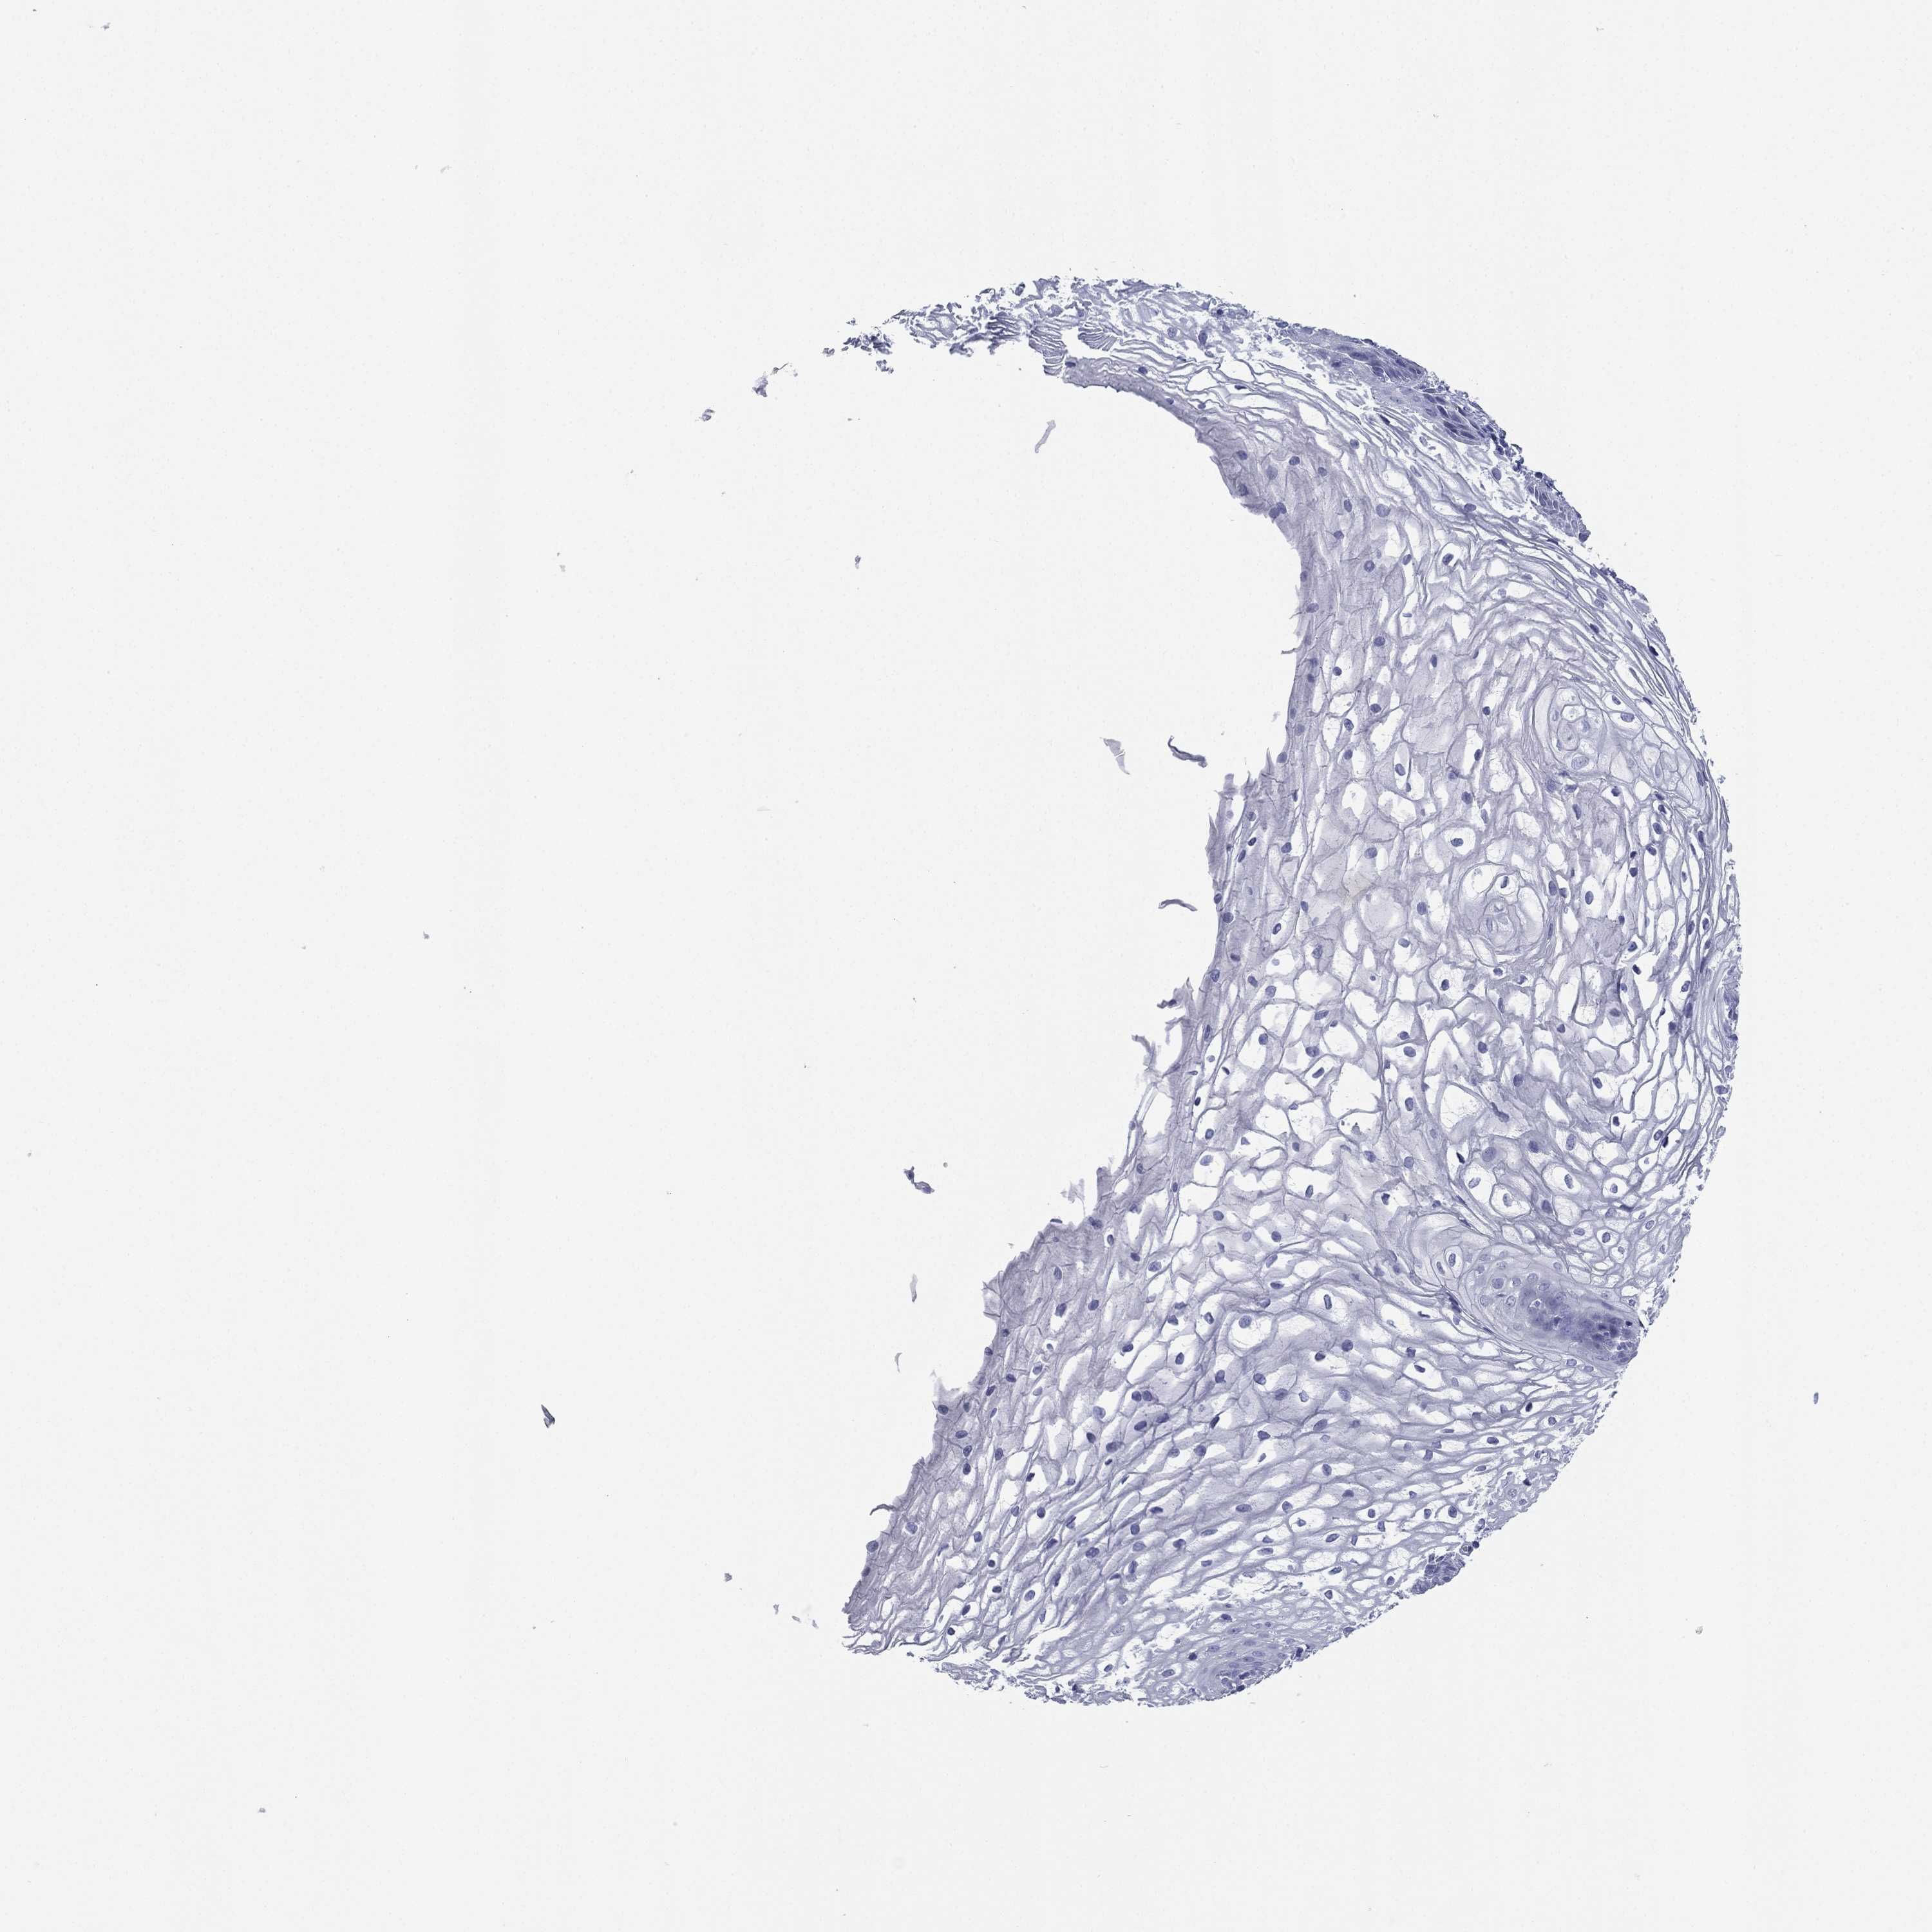

FCER2